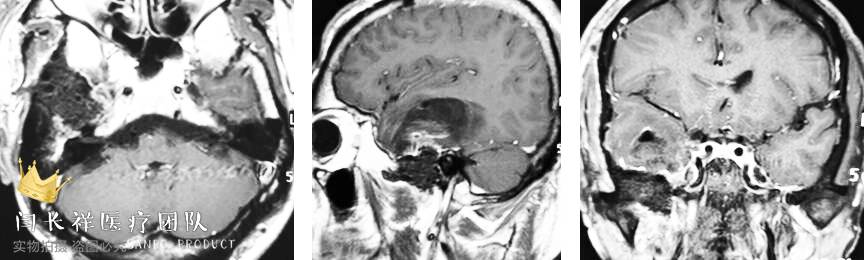

术后6小时复查头部CT示肿瘤切除满意。

术后头部增强MRI示肿瘤切除满意。